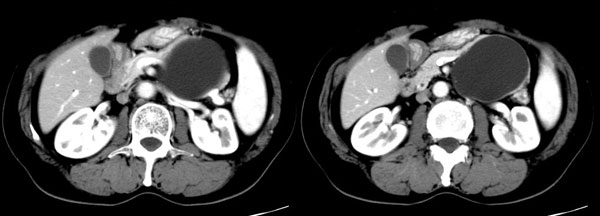

参照ct片,经皮穿刺,抽出透明液体60ml,随后置入引流管引流,囊液细胞学检查阴性,胰酶检查阴性。采用无水乙醇灌注治疗。4天后囊腔闭锁,无液体渗出,予以拔管。

置管后造影,显示囊腔直径约5cm,囊壁光整,正位、双斜位造影均未见造影剂外溢,与胰腺无交通